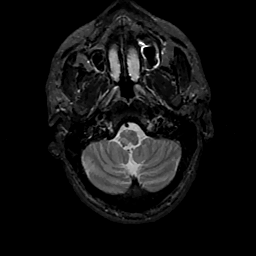

MR Study #11, May 5, 1991 -- Slice #6